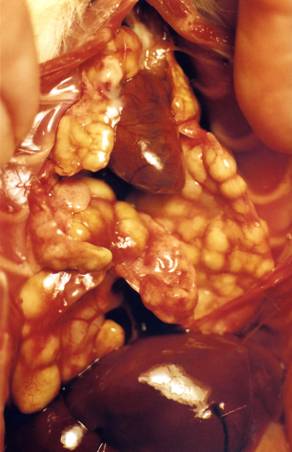

This picture shows most of the deeper abdominal organs after

the intestines have been pulled up out of the way. The other kidney and ovary are on the

other side out of sight. The spleen has been pulled over to the

left of the picture but is usually between the stomach and kidney. The other organs not visible are the bladder

(at the base of the uterus), the pancreas (between the stomach and spleen), and

the cecum (lower right abdomen).